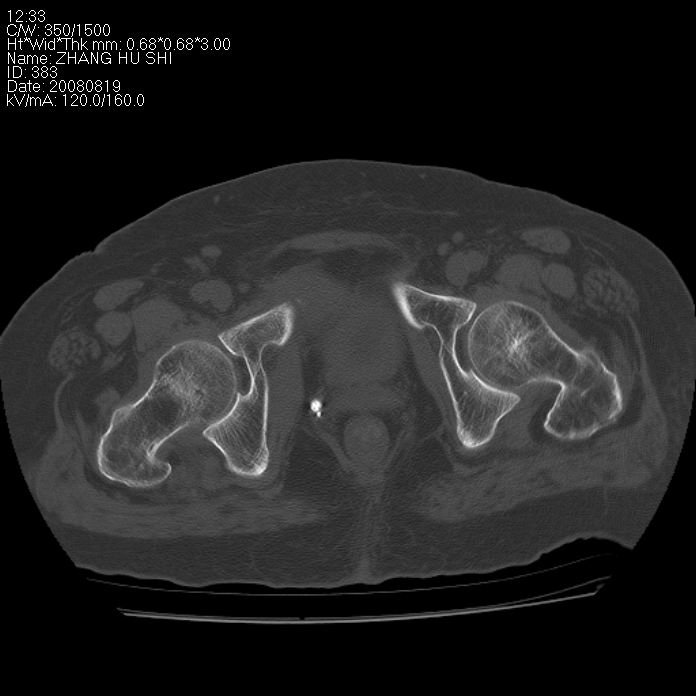

标题: CT15287:女 93岁 右髋关节疼痛 原左侧粗隆间骨折 CT发现右耻 [打印本页]

标题: CT15287:女 93岁 右髋关节疼痛 原左侧粗隆间骨折 CT发现右耻

支持转移并周围软组织侵犯右闭孔内肌侵犯,但tb不能完全除外。

耻骨软骨肉瘤可能性大